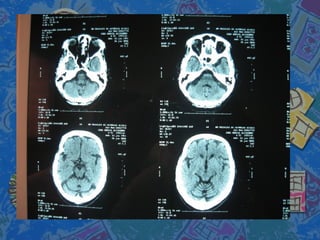

Se solicita TAC craneal con atrofiaSe solicita TAC craneal con atrofia

corticosubcotical cerebral ycorticosubcotical cerebral y

cerebelosacerebelosa

Se solicita TACcraneal con atrofiaSe solicita TAC craneal con atrofia corticosubcotical cerebral ycorticosubcotical cerebral y cerebelosacerebelosa